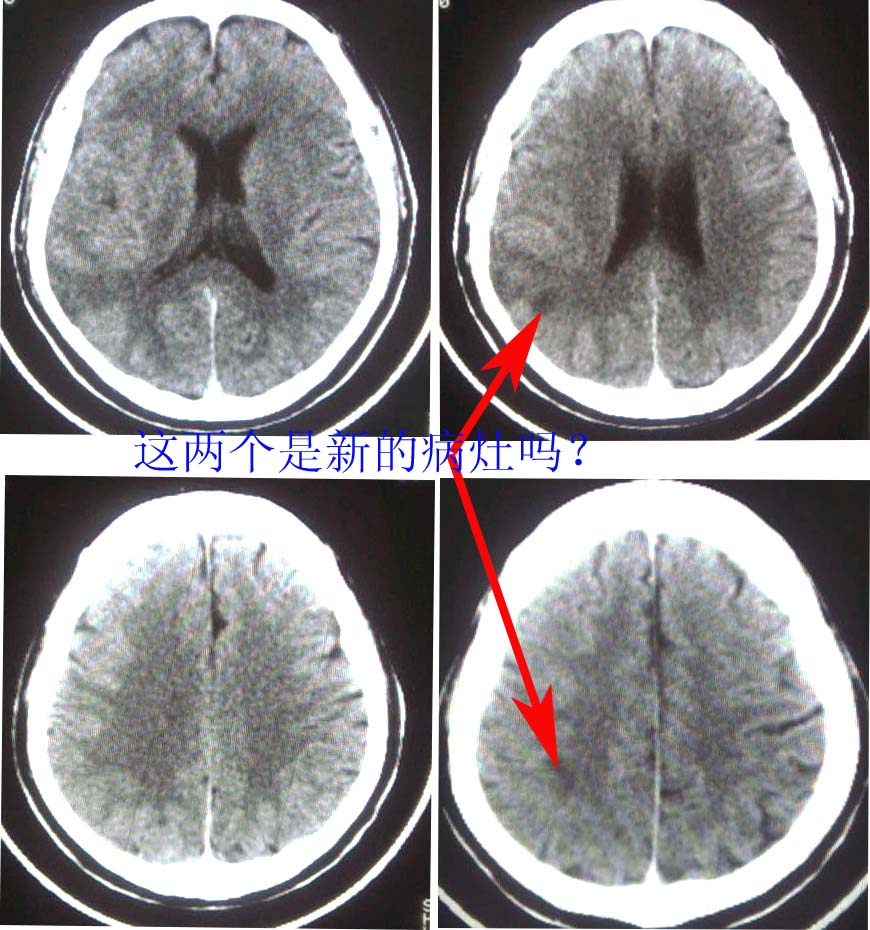

这是一个49岁 男性患者,近两天头痛,自感言语不利。既往有脑梗塞病使。麻烦各位老师看看有没有新的病灶。谢谢!

对不起,图片发颠倒了

是新发病灶,另外左枕叶可见软化灶形成.

支持,新病灶密度不是很低,境界不很清楚